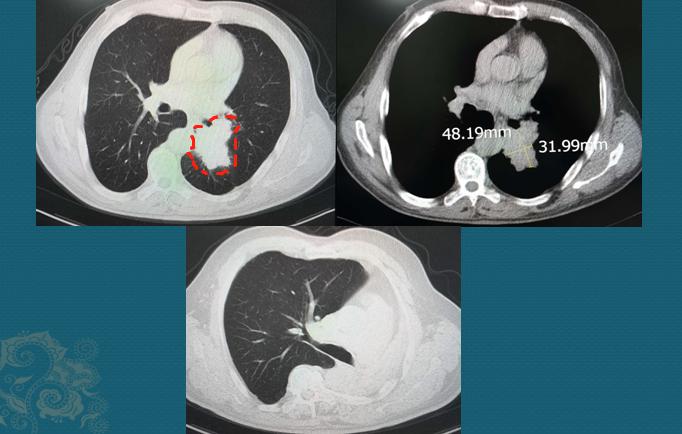

这是一位64岁男病人,老烟民,牙齿都是焦黄的,反复咳嗽、痰多40天,胸闷10天,CT发现左侧中心型肺癌:

下面的图是手术后3.5年复查,左肺全切,没有复发

中心型肺癌手术要慎重,需要术前充分评估,除了排查有无远处转移之外,还要重点观察对肺门血管、气管的侵袭范围,判断有无手术条件。